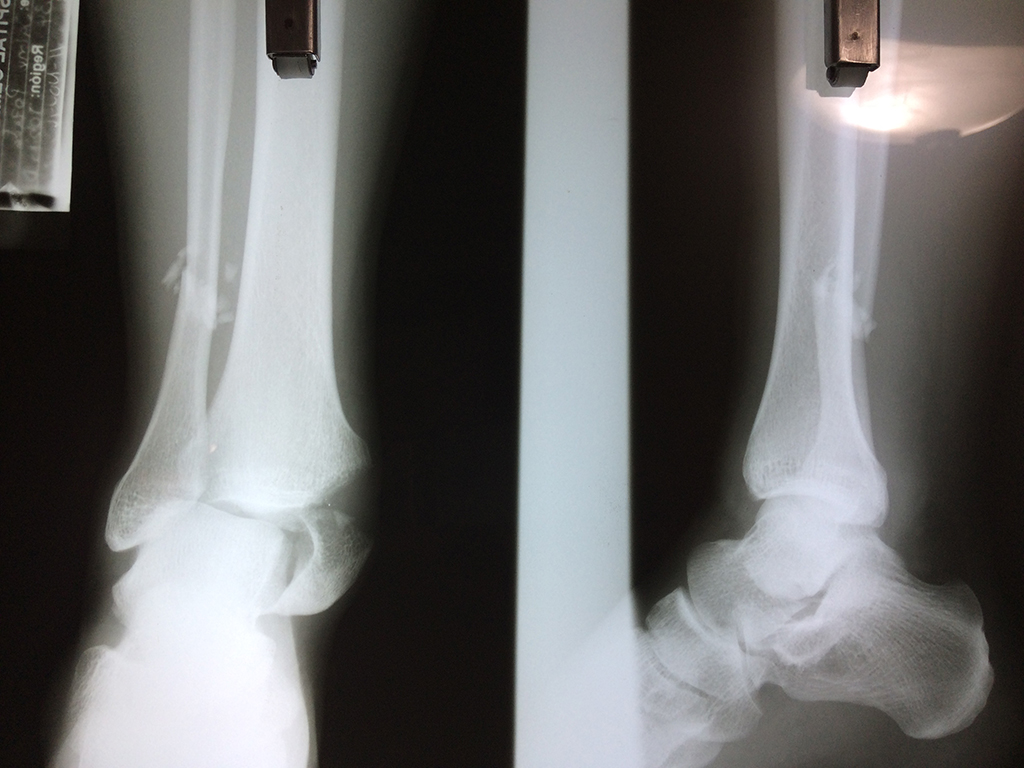

Una fractura de tobillo es la rotura de uno o más de los huesos del tobillo. Estas fracturas pueden ser:

Algunas fracturas de tobillo pueden requerir cirugía si:

- Los extremos de los huesos están desalineados entre sí (desplazados).

- La fractura se extiende hasta la articulación del tobillo (fractura intra-articular).

- Los tendones o ligamentos (tejidos que sujetan los músculos y los huesos entre sí) están rotos.